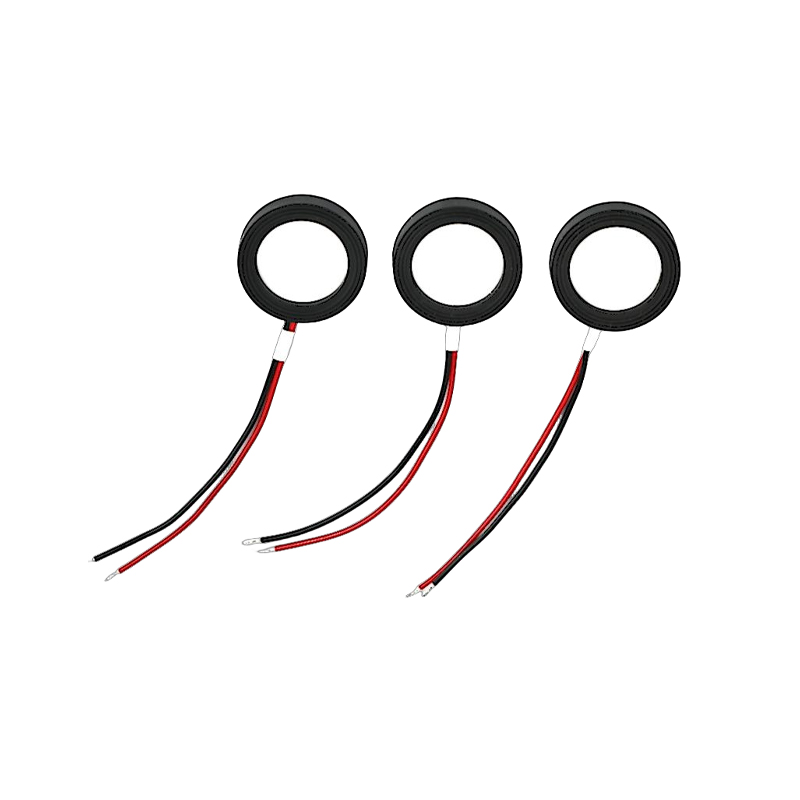

Medyczne tabletki do nebulizatora siatkowego to precyzyjne elementy stosowane w urządzeniach medycznych do przekształcania leków lub roztworów w drobne cząsteczki aerozolu w celu leczenia różnych chorób układu oddechowego, takich jak astma i przewlekła obturacyjna choroba płuc (POChP) itp., poprzez inhalację. Konstrukcja i dobór materiału arkusza nebulizatora mają kluczowe znaczenie dla zapewnienia skutecznego podawania leku i komfortu pacjenta. Arkusz membrany ze stali nierdzewnej jest dziurkowany w blasze stalowej tysiącami drobnych otworów o oczkach 2-3 μm za pomocą technologii wiercenia laserowego w precyzyjnym procesie laserowym, a następnie jest ściśle połączony z okrągłym arkuszem ceramicznym piezoelektrycznym, który przekształca częstotliwość rezonansową arkusza piezoelektrycznego w energię wibracji o wysokiej częstotliwości poprzez sygnał wyjściowy płytki sterownika PCB i szybko rozkłada płynny lek na drobne cząsteczki aerozolu. Krople te nazywane są również medianą wielkości cząstek. Gdy mediana wielkości cząstek D50 osiąga >60% lub więcej, cząstki będą wystarczająco małe, aby podczas oddychania móc dotrzeć głęboko do płuc do powierzchni pęcherzyków płucnych, poprawiając w ten sposób skuteczność wchłaniania leku i efekt terapeutyczny. Arkusz nebulizatora z mikrosiatką medyczną ma głównie kilka form, arkusz nebulizatora z mikrosiatką ze stali nierdzewnej, arkusz nebulizatora medycznego z niklowo-palladem, arkusz nebulizatora medycznego z polimeru PI i tak dalej. Wszystko powyższe odbywa się poprzez piezoelektryczną konwersję energii wibracji ceramicznych w celu osiągnięcia efektu atomizacji.

Bezołowiowa ceramika piezoelektryczna jest znana jako „perła” przemysłu piezoelektrycznego, w przyszłości stopniowo zastąpi ona we wszystkich aspektach ceramikę piezoelektryczną na bazie ołowiu, która ma już tę samą wydajność piezoelektryczną, oraz blachę piezoelektryczną na bazie ołowiu. Jest całkowicie nietoksyczny, nieszkodliwy, bezpieczny i przyjazny dla środowiska, nie zawiera ołowiu, antymonu i innych metali ciężkich oraz innych pierwiastków objętych ograniczeniami Rohs, wysoka temperatura Curie Tc-328°C, bardzo niska strata elektryczna TangentLoss Dlatego bezołowiowy piezoelektryczny chip do atomizacji medycznej ma wielką wartość handlową i wartość uniwersalną, naprawdę nietoksyczną i przyjazną dla środowiska, bezołowiową ceramikę piezoelektryczną, a także niezanieczyszczającą, piezoelektryczną wydajność porównywalną z ceramiką na bazie ołowiu, stanie się popularną przyjazną dla środowiska ceramiką piezoelektryczną. Po latach badań i rozwoju, po ciągłych testach i eksperymentach, firmie udało się wyprodukować bezołowiowy medyczny chip atomizujący, który pozwala uzyskać taką samą ilość atomizacji jak chip atomizujący na bazie ołowiu, a także wymagania dotyczące cząstek o tej samej średnicy. Bezołowiowy chip nebulizatora medycznego Mesh z pewnością zabłyśnie i znajdzie szerokie zastosowanie.

Rozpylacz ultradźwiękowy to urządzenie wykorzystujące zasadę wibracji ultradźwiękowych (konwersji energii) do zamiany cieczy na drobne kropelki. Zasadą działania są unikalne właściwości piezoelektryczne ceramiki piezoelektrycznej. Element atomizujący odbierający odpowiednie wzbudzenie sygnału pola elektrycznego wytworzy odpowiednią częstotliwość oscylacji, poprzez rolę wibracji o wysokiej częstotliwości kawitacji cieczy wyrzucanej z powierzchni wody w celu wytworzenia rodzaju cząstek mgły wodnej, atomizowanych dużą liczbą jonów ujemnych i małych cząstek cząsteczek, może osiągnąć wzrost wilgotności otoczenia, rolę świeżego powietrza. Powierzchnia atomizera jest pokryta emalią szklistą o wysokiej temperaturze 800 stopni, aby chronić srebrne elektrody arkusza piezoelektrycznego, zwiększyć odporność atomizera na kwasy i zasady oraz odporność na utlenianie, a także zwiększyć żywotność atomizera. Szeroko stosowany w nawilżaczach wewnętrznych, oczyszczaczach powietrza, leczeniu nebulizatorami medycznymi i samochodach kosmetycznych, e i innych dziedzinach, ale nadaje się również do magazynów, fabryk, nawilżania, dezynfekcji, aby stworzyć atmosferę sprzętu nawilżającego. Tabletki zamgławiające stosuje się głównie w nawilżaniu przemysłowym, zamgławianiu medycznym, zamgławianiu aromaterapeutycznym, nawilżaniu środowiska, zamgławianiu ogrodu i innych scenach.